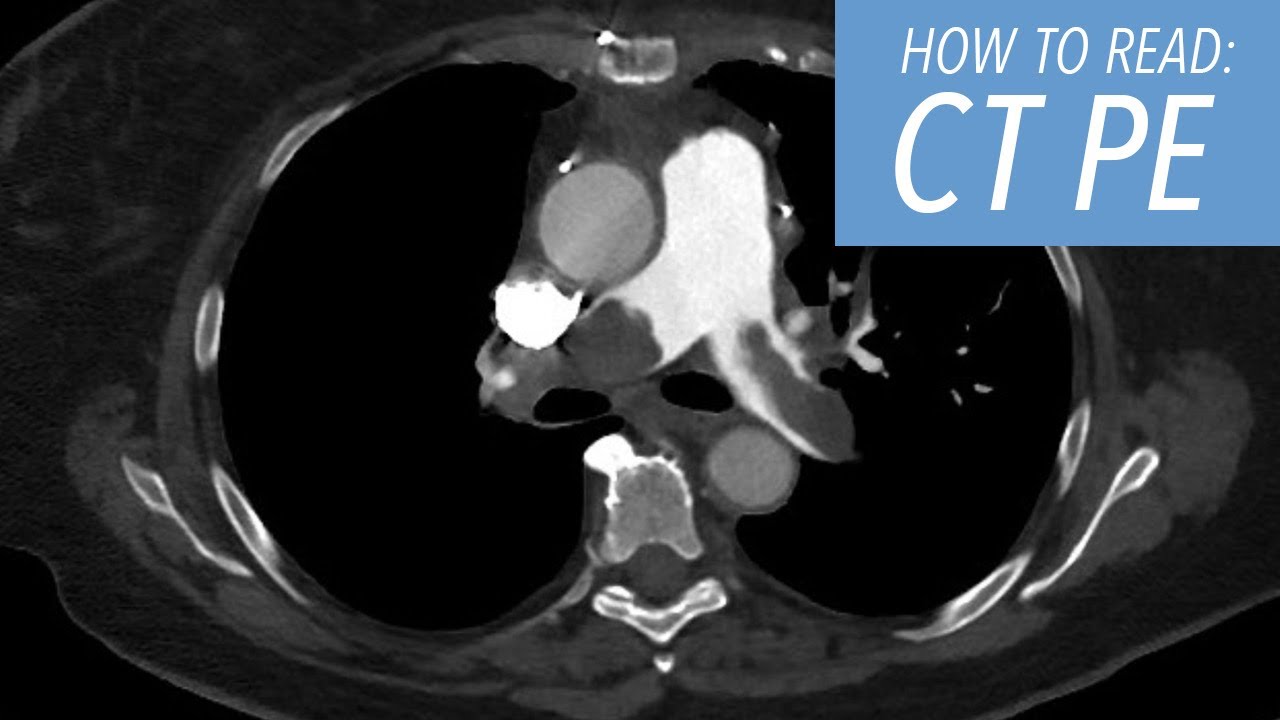

so let's look at this unguided study on a young woman who came in with chest pain and has what looks like a small dissection in the a semi thoracic aorta now we have all seen the pulsation artifact that looks like a dissection and in this case very well could be a pulsation artifact but she had a very strong clinical suspicion for dissection and we couldn't be absolutely sure that this wasn't a dissection so she was imaged the following day with a gated study look at the difference the case on the right there is no artifact

there is no dissection and there is no question so patient with chest pain and a concern for a sending thoracic dissection you have to perform a gated acquisition same patient every set of presentations axial sagittal coronal looked like there was a dissection on the first undated study and is clearly normal on the gated acquisition coronary artery imaging we need a gated acquisition so that we can evaluate these small vessels we're at a point in the cardiac cycle where the motion artifact is minimized here is a patient who had was being imaged actually for the ascending